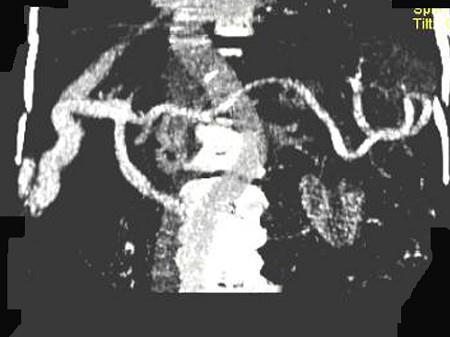

问题 女,70岁,发现乙型肝炎10年,3年前CT诊断为肝硬化,CT检查见图,最可能的诊断是 ( )

选项 A.肝癌 B.肝硬化、肝血管瘤 C.肝硬化、门脉瘤样扩张 D.肝门脉畸形 E.肝转移瘤、门脉扩张

答案 C